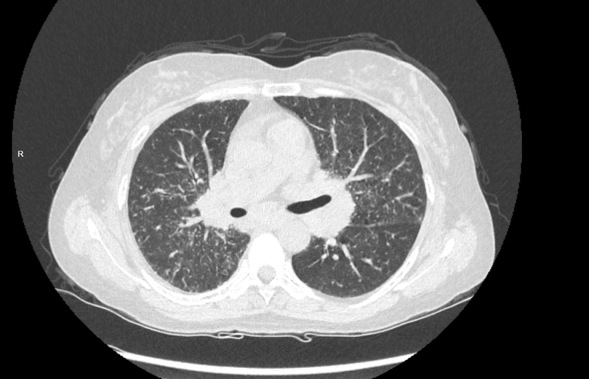

胸部CT:纵膈淋巴结肿大 双肺多发粟粒结节影

7组淋巴结肿大

4R组淋巴结肿大